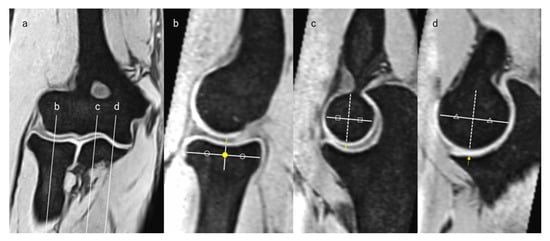

2.5. Measurement of JSW

2.6. Assessment of HACOV